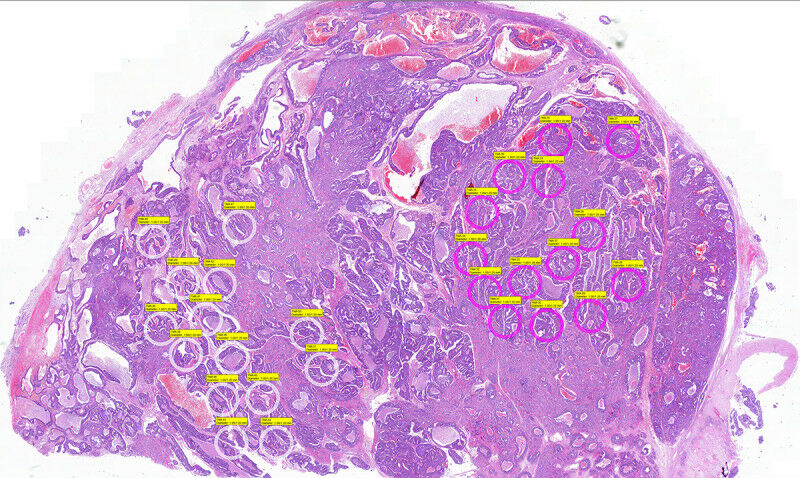

Brain metastasis of prostate cancer with selected intratumoral areas (pink and white circles) for undergoing molecular analyses. © Antonio Rodriguez, Dept. of Pathology and DBMR

Brain metastasis of prostate cancer with selected intratumoral areas (pink and white circles) for undergoing molecular analyses. Antonio Rodriguez, Dept. of Pathology and DBMR - Researchers at the University of Bern and University Hospital Bern have achieved a breakthrough in a particularly aggressive form of prostate cancer. In tissue samples from advanced brain metastases, they were able to establish the genetic profile of the cancer cells. These findings show for the first time that affected patients could benefit from target treatment, from which they have so far not been eligible. Around 6,600 men are diagnosed with prostate cancer in Switzerland every year. It is the second most common cause of cancer-related death in men after lung cancer.